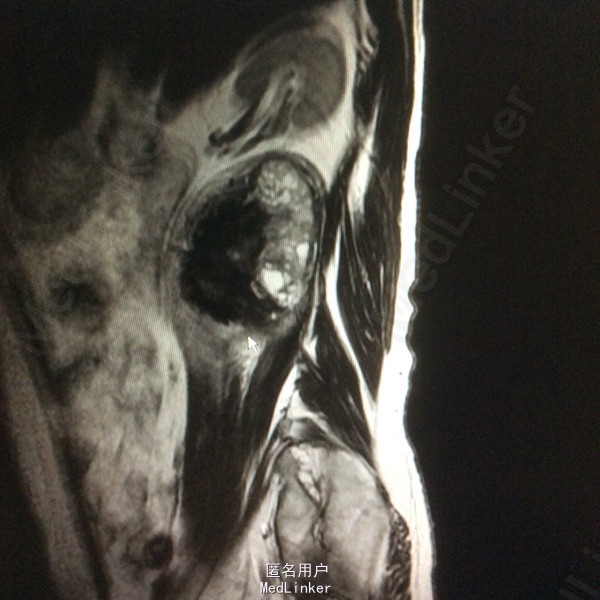

患者双下肢无明显浅感觉减退,肌力V级,肌张力不高,二便控制满意,病理征阴性。 腰椎核磁:腰1-4椎体右侧右肾下方团块状占位,大小约8#⃣6.8Cm,等T1长T2信号 腰椎Ct:占位周围见弧形钙化灶